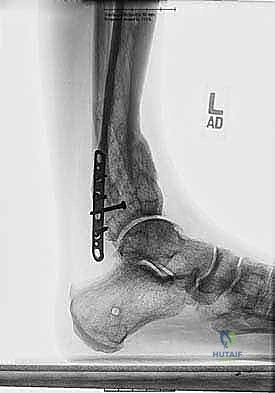

| وجه المقارنة | العلاج التحفظي (بدون جراحة) | الجراحة بالتثبيت الداخلي (شرائح ومسامير) | الجراحة بالتثبيت الخارجي (طريقة د. هطيف المفضلة للتشوهات المعقدة) |

| آلية العلاج | أحذية طبية، دعامات، علاج طبيعي ومسكنات. | قطع العظم وتثبيته فوراً في الوضع الصحيح باستخدام شريحة معدنية داخلية. | قطع العظم وتركيب هيكل معدني خارجي متصل بالعظم بأسلاك، مع تصحيح تدريجي. |

| القدرة على تصحيح التشوهات | لا يصحح التشوه، بل يخفف الأعراض مؤقتاً فقط. | ممتاز للتشوهات البسيطة وذات البعد الواحد (مثل التقوس فقط). | استثنائي. يصحح التشوهات المعقدة، ثلاثية الأبعاد، ويعالج قصر الساق في نفس الوقت. |

| التأثير على الأنسجة الرخوة (الجلد) | لا يوجد تأثير. | يتطلب شقاً جراحياً كبيراً، مما قد يسبب مشاكل في التئام الجرح، خاصة إذا كان الجلد متضرراً مسبقاً. | أقل تدخل جراحي. يتم عبر ثقوب صغيرة، مما يحمي الجلد والأنسجة الرخوة والأوعية الدموية. |

| خطر العدوى (الالتهابات) | لا يوجد. | خطر وارد، وإذا حدث التهاب في الشريحة، يجب إزالتها وعمل جراحات متعددة. | خطر التهاب سطحي حول الأسلاك يمكن علاجه بسهولة بالمضادات الحيوية الموضعية والفموية. |

| القدرة على تعديل التصحيح بعد الجراحة | غير ممكن. | غير ممكن. إذا كان هناك خطأ، يتطلب جراحة أخرى. | ميزة حصرية. يمكن تعديل زوايا التصحيح يومياً في العيادة دون تخدير حتى الوصول للمثالية. |

| التحميل والمشي | مسموح. | يمنع المشي على الساق لعدة أسابيع أو أشهر حتى يلتئم العظم. | مسموح مبكراً. المريض يشجع على المشي والتحميل الجزئي على المثبت الخارجي، مما يسرع بناء العظم. |

كما يوضح الجدول، يتفوق التثبيت الخارجي في الحالات المعقدة، حالات ضعف الأنسجة الرخوة، وحالات قصر الأطراف المترافقة مع التشوه.